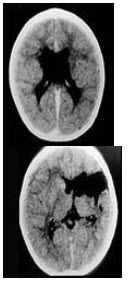

患儿,男,1岁,运动发育落后半年。生后5分钟Apgar评分5分。家族史阴性。查体:智力正常,双上肢活动正常,双下肢肌张力增高,腱反射亢进,踝阵挛阳性。CT检查如图。

(单选题)本病最可能诊断为( )

A:椎管内肿瘤

B:脑炎后遗症

C:遗传性痉挛性截瘫

D:脑性瘫痪

E:Louis-Barr综合征